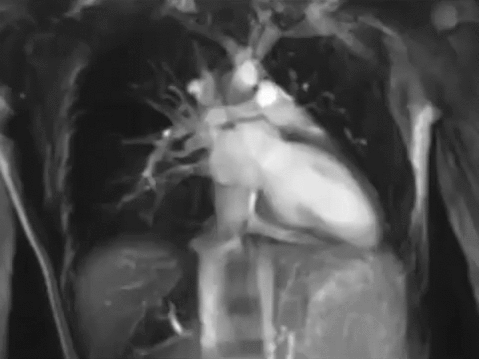

Сердце человека (лат. cor, греч. ϰαρδία [kardia]) — это конусообразный полый мышечный орган, в который поступает кровь из впадающих в него венозных стволов и перекачивающий её в артерии, которые примыкают к сердцу. Полость сердца разделена на два предсердия и два желудочка. Левое предсердие и левый желудочек в совокупности образуют «артериальное сердце», названное так по типу проходящей через него крови, правый желудочек и правое предсердие объединяются в «венозное сердце», названное по тому же принципу. Сокращение сердца называется систолой, а расслабление — диастолой[B: 1].

Сердце состоит из четырёх отдельных полостей, называемых камерами: левое предсердие, правое предсердие, левый желудочек, правый желудочек. Они разделены перегородками. В правое предсердие входят верхняя полая и нижняя полая вены, в левое предсердие — лёгочные вены. Из правого желудочка и левого желудочка выходят, соответственно, лёгочная артерия (лёгочный ствол) и восходящая аорта. Правый желудочек и левое предсердие замыкают малый круг кровообращения, левый желудочек и правое предсердие — большой круг. Сердце расположено в нижней части переднего средостения, большая часть его передней поверхности прикрыта лёгкими с впадающими участками полых и лёгочных вен, а также выходящими аортой и лёгочным стволом. В полости перикарда содержится небольшое количество серозной жидкости[B: 2][B: 4].

Стенка левого желудочка приблизительно в три раза толще, чем стенка правого желудочка, так как левый должен быть достаточно сильным, чтобы вытолкнуть кровь в большой круг кровообращения для всего организма (сопротивление потоку крови в большом круге кровообращения в несколько раз больше, а давление крови в несколько раз выше, чем в малом круге кровообращения).